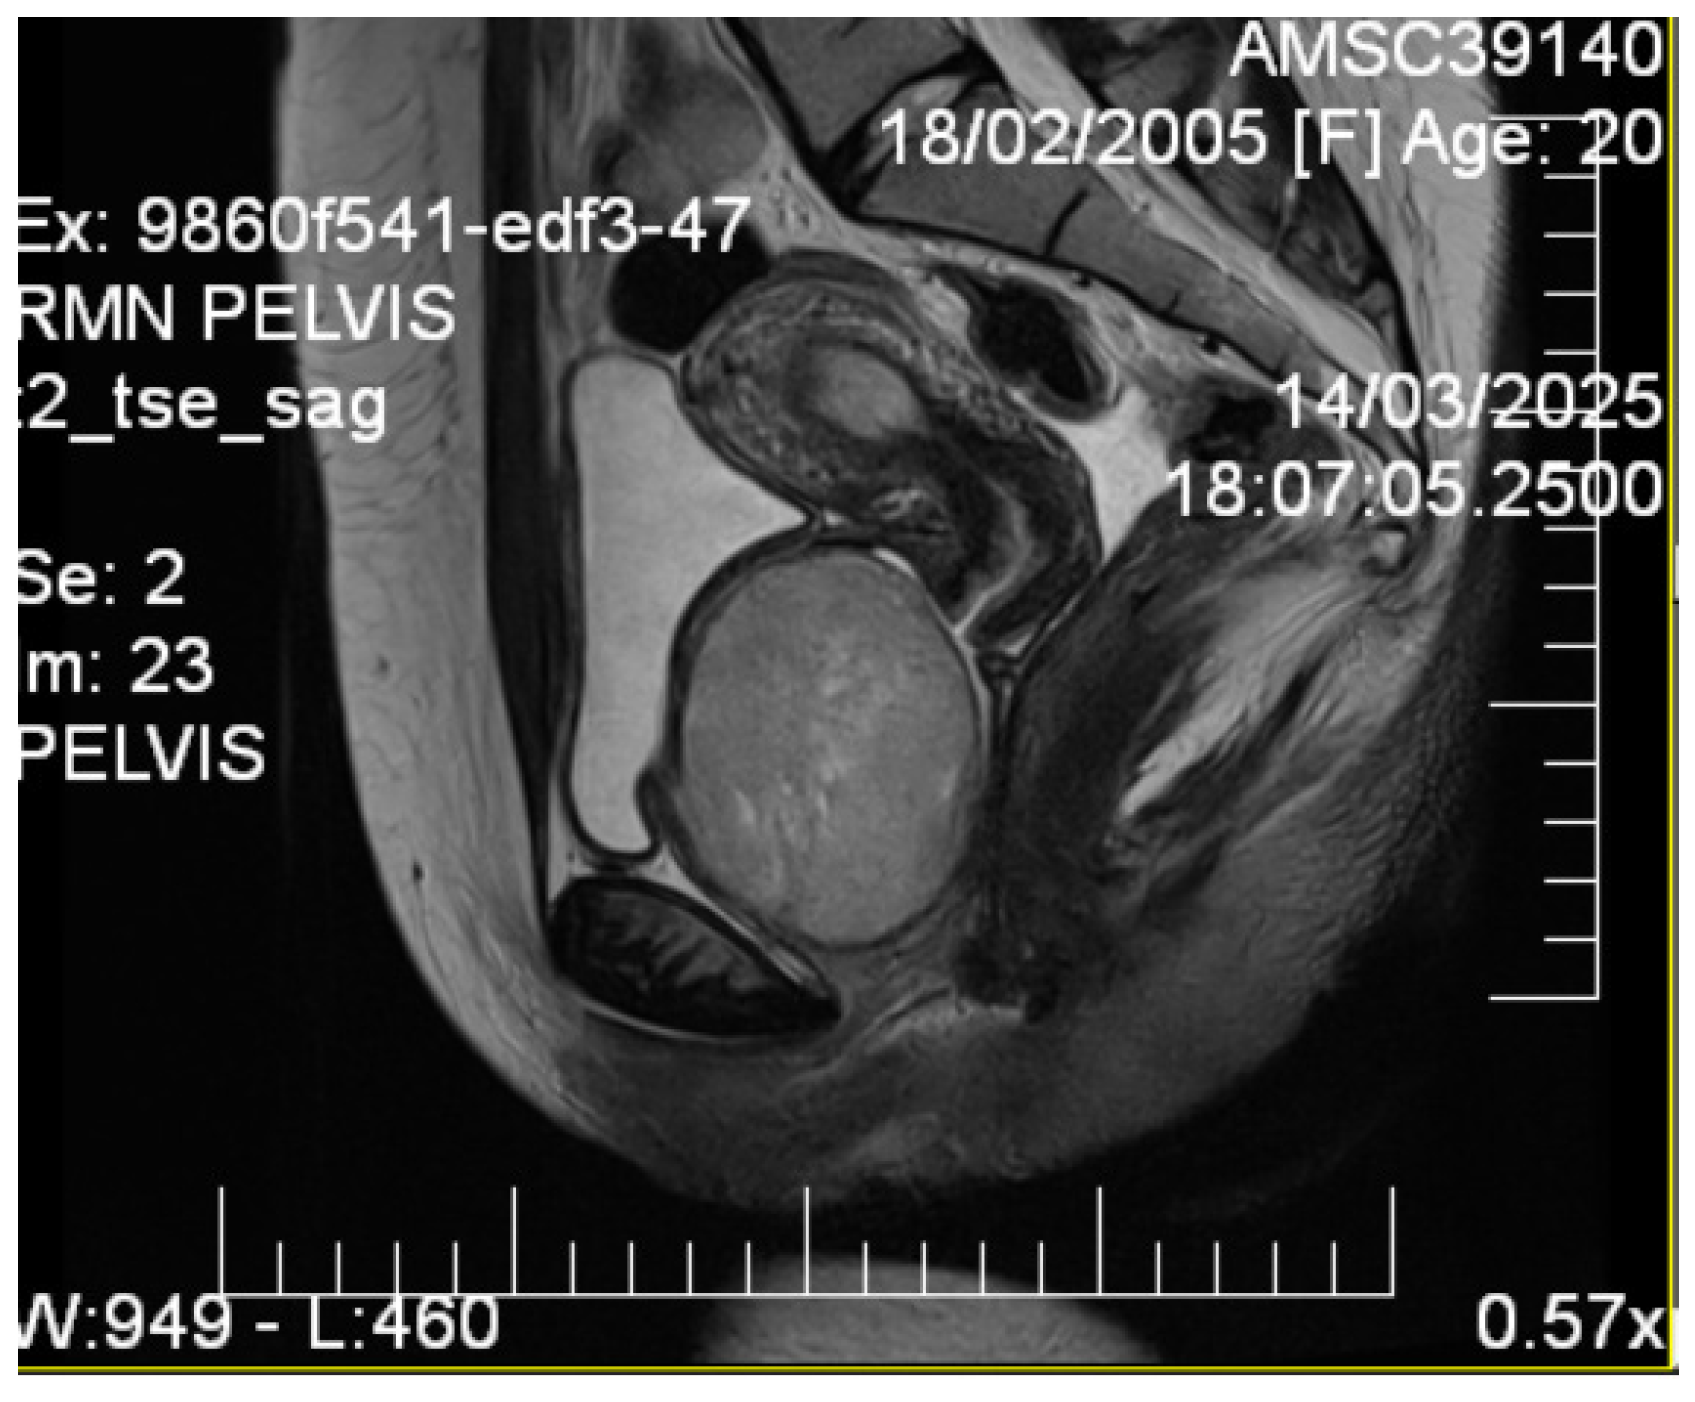

2.4. Imaging Studies

3.1. Imaging Characteristics and Diagnostic Precision

- Related abnormalities: Recording related concomitant septate uterus helps interpret possible developmental associations [11].

- MRI is decisive in characterizing tissues.